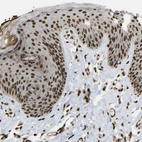

Immunohistochemical staining of human fallopian tube shows strong nuclear positivity in glandular cells.